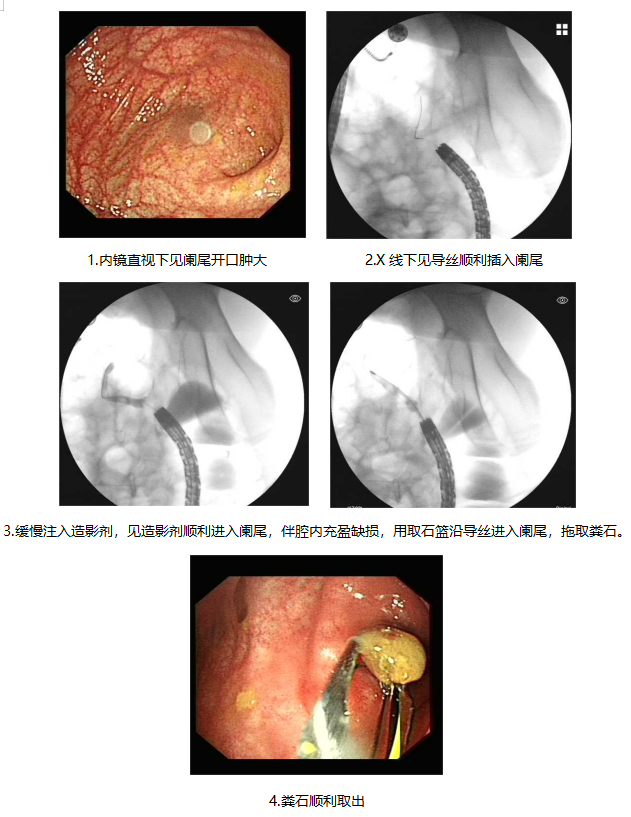

消化内科一病区成功为一位患者实施了内镜下阑尾治疗术,不开刀,无创伤,整台手术共计27分钟,既解决了阑尾炎的困扰,又实现了阑尾的保留。

消化内科一病区李俊主任了解病情后,考虑到患者年龄较小,组织团队制定了周密的手术计划,详细向患者家属介绍手术的操作过程、微创性及优缺点。经患者家属同意后,在消化内镜室行内镜逆行性阑尾炎治疗术,术中将阑尾腔内大量粪石及脓性分泌物冲出,术后查体患儿腹痛明显缓解,择期出院。

内镜逆行性阑尾炎治疗(endoscopic retrograde appendicitis therapy, ERAT)与常规外科阑尾切除术有所不同,其理念围绕着超级微创术展开,是从人体自然腔道进入,通过内镜插入回盲部,进行插管、冲洗减压、粪石取出、扩张狭窄阑尾腔、放置阑尾支架以及引流脓液等多种治疗手段来治疗阑尾炎,其优势体现在疼痛迅速缓解、保留阑尾完整性和功能、术后并发症少、术后患者恢复迅速、手术费用较低等方面。